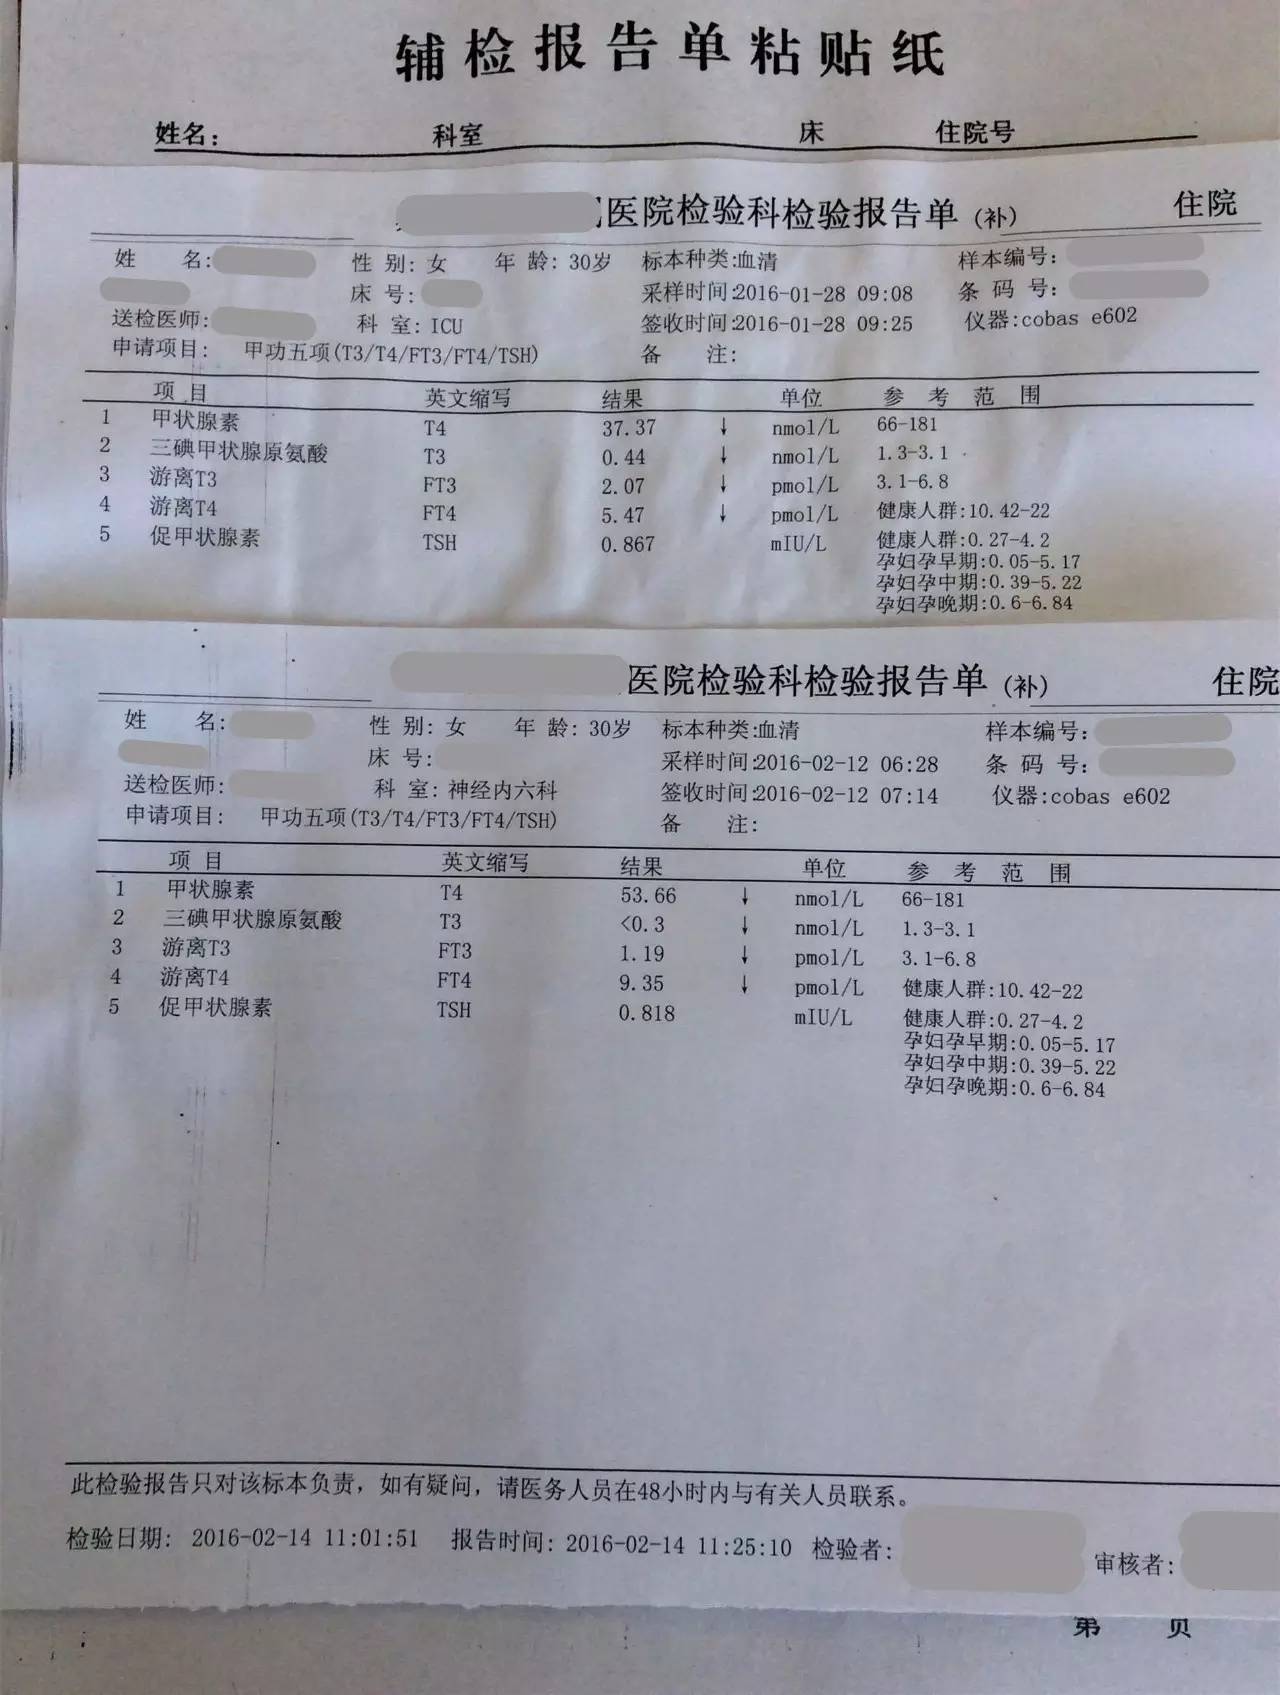

▼患者检查报告资料

1.甲状腺功能减退症:因为患者属于继发性甲状腺功能减退症,因此根据FT4水平来调整优甲乐的剂量即可,目前加量到100μg/天,同意这种调整;